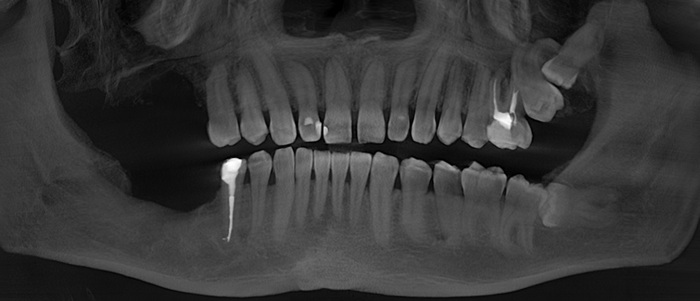

Контрольный рентгеновский снимок:

Вот так было:

А как стало на промежуточном этапе:

Согласитесь, выглядит очень даже неплохо, если опустить цвет.